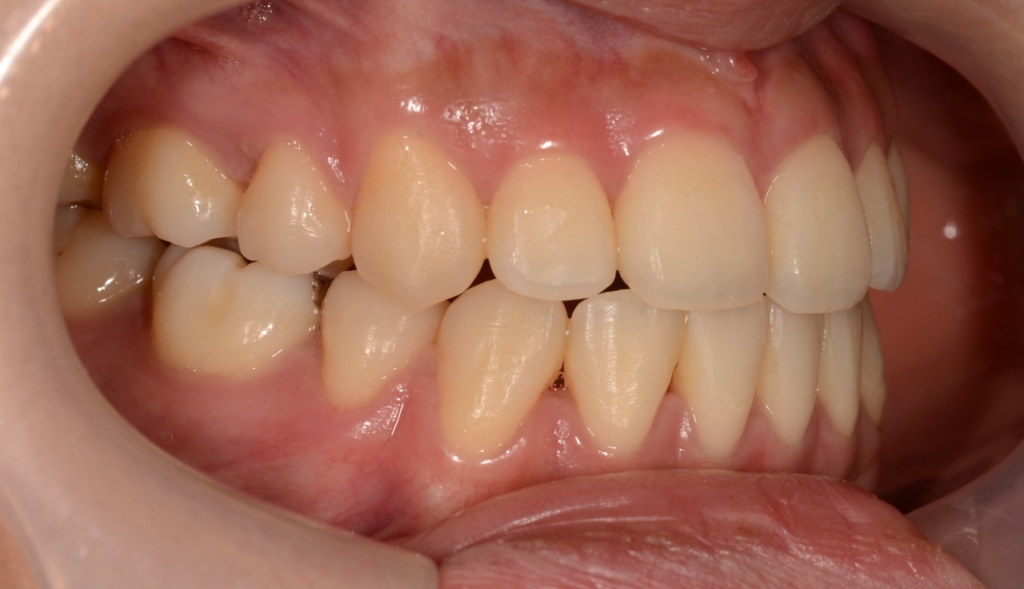

ついでに、歯並びの比較です

上段が矯正治療前、下段が矯正治療後

矯正治療の結果、Eラインに.しっかり収まりました。

口元の下口唇部を中心とした突出感(口ごぼ)は無くなり、狙い通りに口元をスッキリさせることが出来たように思います。 横顔も締まった良い感じに収まったように思えます。